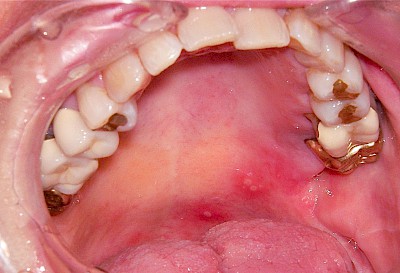

Aphte

Aphten lassen sich gut von Herpes unterscheiden, da Aphten in aller Regel nur einzeln und nicht Gruppiert auftreten. Die Ursachen sind bis heute nicht ganz geklärt. Unter anderem werden Viren aber auch Veranlagung diskutiert. Aphten sind vor allem nur an nicht-verhornten Schleimhautbereichen (Wange, Lippeninnenseite, Mundboden und Rachen) auf. In seltenen Fällen können die Blasen sehr groß sein oder doch in großer Zahl auftreten – hier sind Störungen des Immunsystems (Auto-Immunerkrankungen) häufig die Ursache.

Beispiele26 Bilder